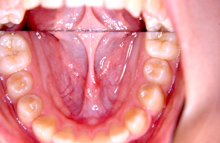

知多市大興寺在住 I.A様(女性)

I.A様は上下の前歯の歯並びがガタガタの叢生が主訴で来院されました。

矯正相談で叢生の場合には歯を移動させ整えるにはスペースが必要で、

スペースの獲得には抜歯の必要性をお話した後、診断のための資料採取をおこないました。

診断の結果、側貌(プロファイル)が良好なため抜歯を行なうことなく治療ができることをお伝えしました。

了解を得られましたので診断時にお渡しした治療計画書を提出してもらい、治療を開始することにいたしました。

上下顎の前歯に叢生(ガタガタ)がみられ、歯列弓の狭窄もすこしあります。臼歯関係は1歯対2歯です。

上顎歯列弓をQ.H(クワドヘリックス)という拡大装置にて拡大します。

処置方針どおり抜歯を行なうことなく、動的治療が完了しました。

非抜歯で治療した場合には後戻りに叢生の傾向がみられます。

動的治療を終了しても少なくとも動的治療に費やした年月は保定が必要です。